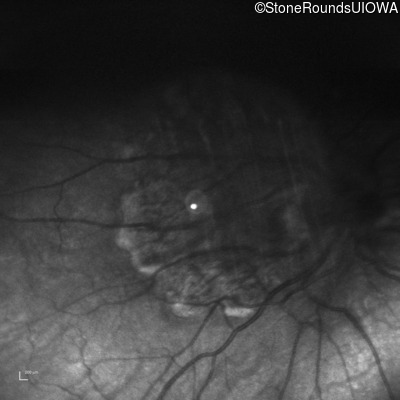

Infrared Fundus Photograph - Right - 20/2000

Exemplar